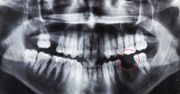

Indie mają kolejny problem. Oprócz epidemii koronawirusa, która sparaliżowała kraj i codziennie pochłania tysiące ofiar, u pacjentów coraz częściej jest diagnozowana tzw. czarna grzybica. Indyjscy lekarze szacują, że z powodu mukormykozy umiera nawet co druga osoba zakażona. Indyjski wariant koronawirusa bardzo rzadko powoduje utratę węchu czy smaku, natomiast bardzo częstym objawem są biegunki. Mogą one prowadzić do dysbakteriozy, czyli zaburzenia flory bakteryjnej jelit, co również zwiększa ryzyko infekcji grzybiczej - mówi prof. Joanna Zajkowska. Czy w związku z obecnością indyjskiej mutacji w Polsce, powinniśmy obawiać się nowych powikłań po COVID?